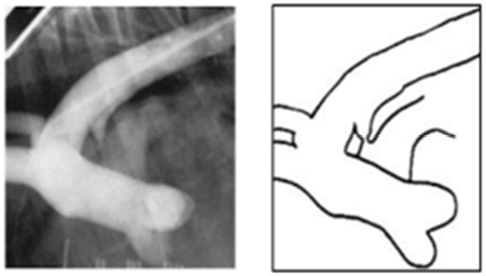

PDA Type

뾰족 + 얇음

ⅡB뭉툭 + 두툼

ⅡA두툼 + 짧음

관이 길다

가장 심각